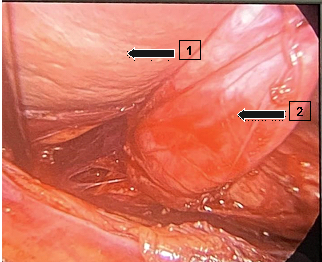

Manometric examination within normal standards. pH-metry, a test that captures any reflux episodes, assesses the pH, intensity, duration and time of occurrence, generating a Meester constant that is above 14.72, indicating GERD. In this test, the patient scored 85.2 on the Meester table, and was diagnosed with orthostatic predominant mixed reflux. In the abdominal ultrasound requested after the first consultation, no alterations were found, as well as in the chest X-ray performed after 2 months. An X-ray of the esophagus, stomach and duodenum (Figure 2), taken the following month after the first consultation, showed the presence of a bulky distal para esophageal diverticulum with debris inside and constant diverticulum esophageal reflux. The stomach and duodenum emptied normally, with no signs of organic damage. After analysing the tests, the patient returned to the office to discuss her diagnosis and treatment. With regard to the treatment of this pathology, surgical treatment is not only indicated due to the presence of the diverticulum, it must be weighed up against the potential risks and benefits of surgery, taking into account the severity of the patient's symptoms and the complications associated with the disease.9 Surgical treatment, when indicated, should focus on motor dysfunction and resection of the diverticulum. The approach should be laparotomy, a less invasive technique with lower morbidity compared to thoracotomy. In addition, a myotomy should be performed to reduce esophageal motor disorders and a partial fundoplication in order to avoid esophageal reflux disease.4

Figure 2 Contrast-enhanced radiography of the esophagus, stomach and duodenum. Arrow (1) epiphrenic diverticulum with contrast inside, Arrow (2) Gastric fundus, Arrow (3) Gastric folds, Arrow (4) Pylorus.